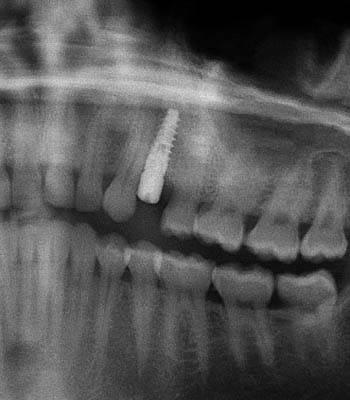

Dental implants are a titanium "root" which can be placed into the jawbone. Once integrated with your bone, the implant can be used to support a crown, a bridge, or secure a complete denture. Dental implants may be used to eliminate partial plates and dentures. The success rates for dental implants are extremely high which is due in part to the fact that root-form implants are made of a biocompatible material, titanium.

Below are a few examples of what DENTAL IMPLANTS can do for you and your smile!

Single Tooth Replacement